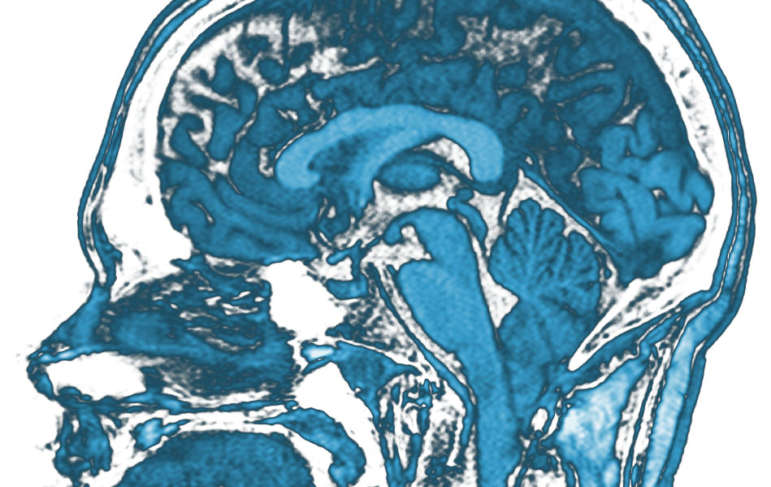

According to the Centers for Disease Control, around 138 people die in the United States every day due to some type of Traumatic Brain injury (TBI). When diagnosing brain injuries, people have to get Computed Tomography (CT) scans, exposing them to radiation that they normally would not be exposed to. Physicians at Washington University Barnes Jewish Medical Center in St. Louis found that they could reduce the amount of CT scans by 30 percent due to a device just approved by the EPA, which was developed by BrainScope Company Inc, a medical neuro-technology company.

The Brainscope study evaluated 91 patients referred for CT scans and were also given a noninvasive BrainScope EEG based Structural Injury Classifier evaluation using a disposable electrode headset, which takes between five and ten minutes. BrainScope says their BrainScope One can assess different brain injuries from concussions to brain bleeding.

The device works by measuring the brain’s electrical activity, which is then filtered using BrainScope’s algorithms. When using this method, the physicians testing the device found that it reduced patient’s exposure to unnecessary radiation by 31 percent.